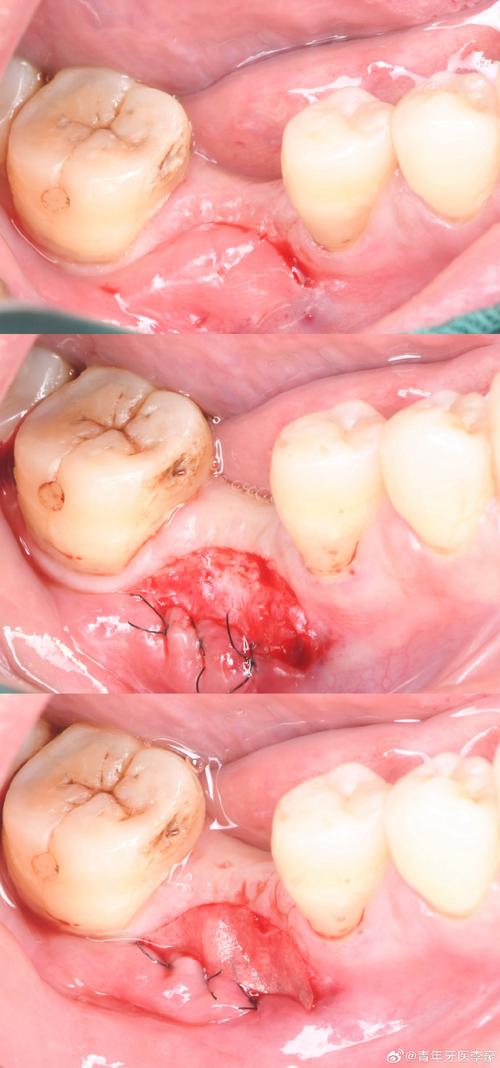

种牙前的磨牙通常指对牙槽骨的修整,当患者因长期缺牙、牙周病或外伤导致牙槽骨出现吸收、骨突或形态不规则时,种植体难以理想植入,此时需通过磨骨(骨修整)改善骨条件,术前医生会借助CBCT(锥形束CT)获取口腔三维影像,通过图片可清晰观察到牙槽骨的厚度、高度及神经管位置,若存在骨量不足或尖锐骨突,需设计磨骨方案,CBCT图片中可见牙槽嵴顶有明显倒凹,或邻牙牙根靠近缺牙区导致骨量不足,此时术中需用高速手机或超声骨刀去除多余骨质,修整出平整的骨面,为种植体提供“扎根”的理想空间,这一过程的图片可记录磨骨前后的骨形态变化,直观展示骨修整的效果。

磨牙操作的精准性直接影响种植牙的成功率,因此医生需严格遵循“少量多次”原则,过度磨除骨组织或牙冠会影响长期效果,术前通过影像学图片评估骨条件,术中实时监控磨骨深度,术后通过咬合图片验证调磨效果,是确保磨牙安全有效的关键,患者可通过这些图片直观了解治疗进展,缓解对未知操作的焦虑。